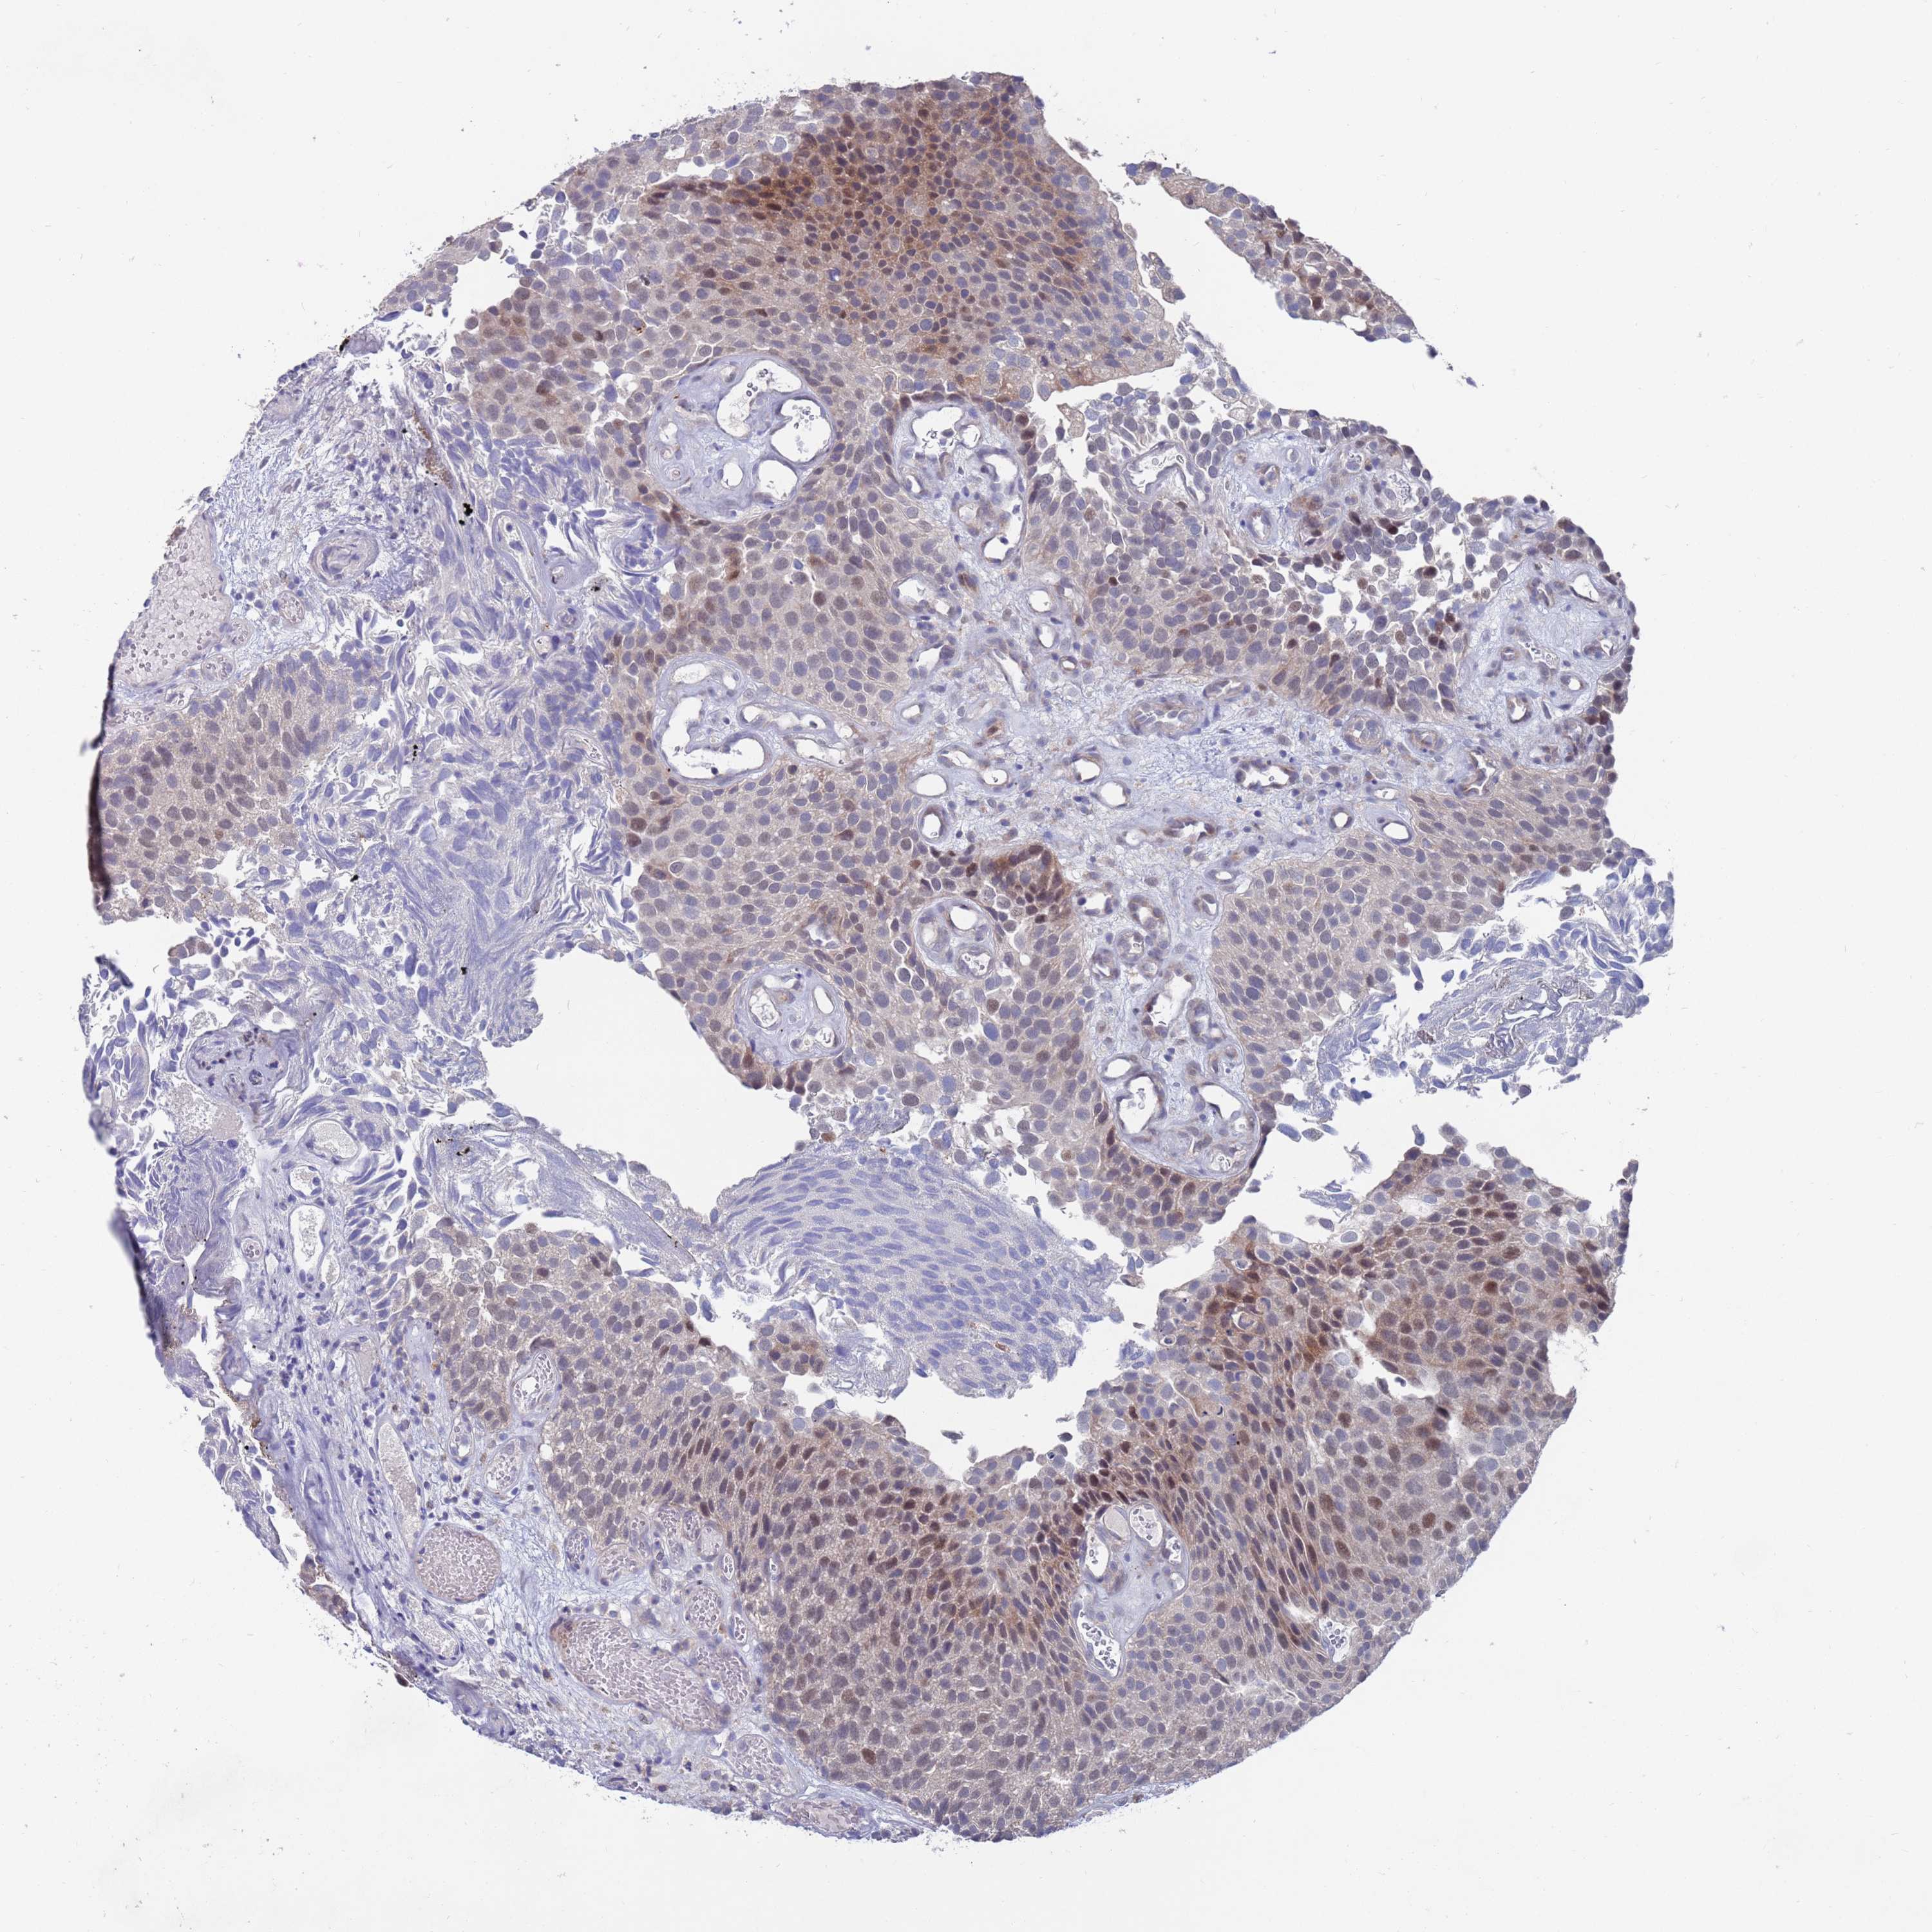

UROTHELIAL CANCER - Protein expressioni

A mouse-over function shows sample information and annotation data. Click on an image to view it in a full screen mode. Samples can be filtered based on level of antibody staining by selecting one or several of the following categories: high, medium, low and not detected. The assay and annotation is described here.

Antibody stainingi

Antibody staining in the annotated cell types in the current human tissue is reported as not detected, low, medium, or high, based on conventional immunohistochemistry profiling in selected tissues. This score is based on the combination of the staining intensity and fraction of stained cells.

Each image is clickable and will lead to virtual microscopy that enables deeper exploration of all samples and also displays staining intensity scores, fraction scores and subcellular localization as well as patient and tissue information for each sample.

Antibody HPA046800

Staining

High

Medium

Low

Not detected

Intensity

Strong

Moderate

Weak

Negative

Quantity

>75%

75%-25%

<25%

None

Location

Nuclear

Cytoplasmic/membranous

Cytoplasmic/membranous,nuclear

Urothelial carcinoma, High grade

Urothelial carcinoma, Low grade